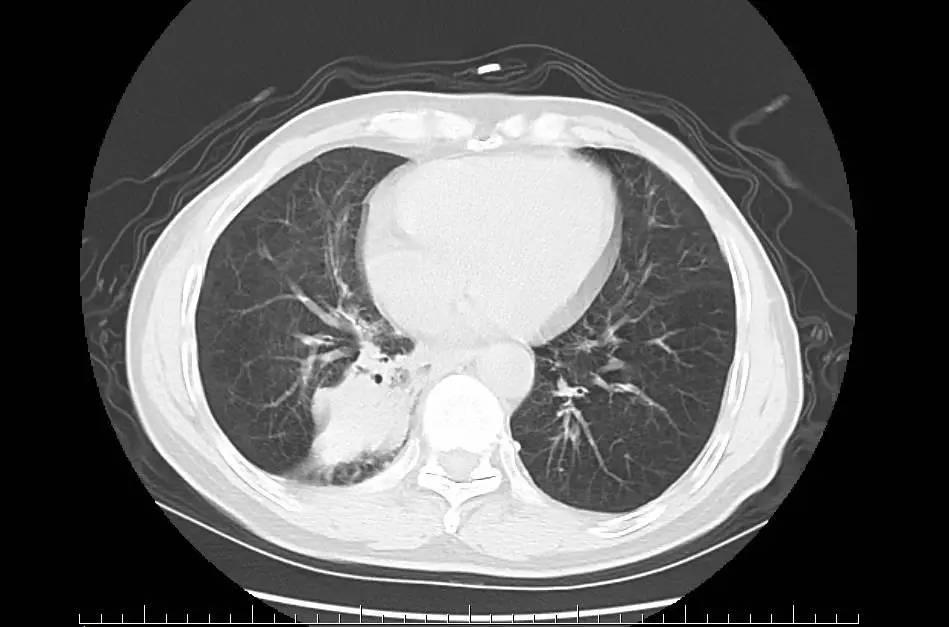

左下肺大面积变白,说明严重炎症,就会出现血现象,严重的甚至会有生命危险。